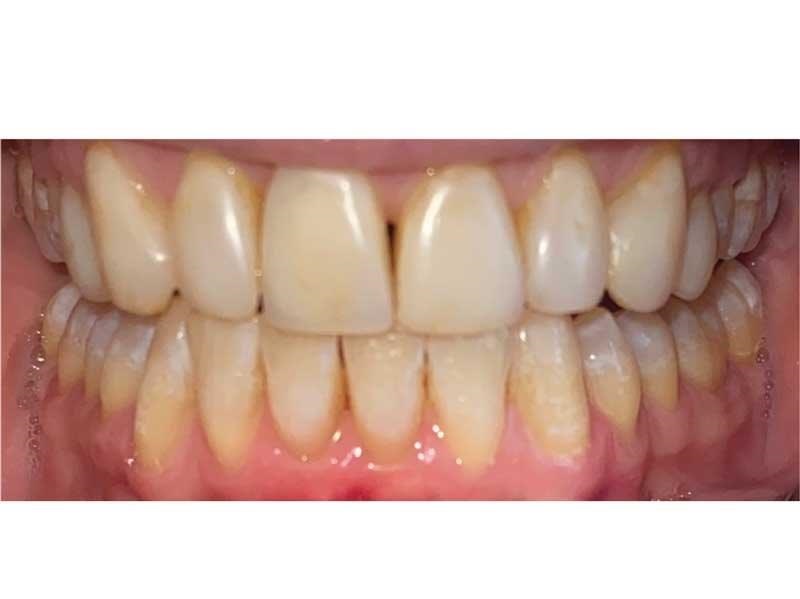

Lorraine drives six hours each way to see me, so I did her case all in one day: TENS bite; sectioned it; built up the lowers with resin to open the vertical (this is one of the cases I didn’t want to send out to a lab); prepped for 10 upper veneers (Fig. 24); temporized uppers; checked occlusion; and refined with TekScan. She came in with broken-down bonding and constant migraines, and left with beautiful temporaries and no more headaches. She came down a few weeks later to insert her gorgeous veneers (Fig. 25, thanks to Aurum Group) and I prepped, scanned, designed and milled and inserted her lower onlays to restore her lower teeth to her new vertical (Figs. 26–31). She has been pain-free ever since.

Conclusion

I see Lorraines all the time. Daily. But I never used to, because I didn’t know what I didn’t know. Once I knew, I couldn’t hold back. Pay attention. Look for clues. These people are all around you. And if you can help them, heal them, free them of their pain and deliver beautiful dentistry in the process, it’s a life-changer. For them and for you.